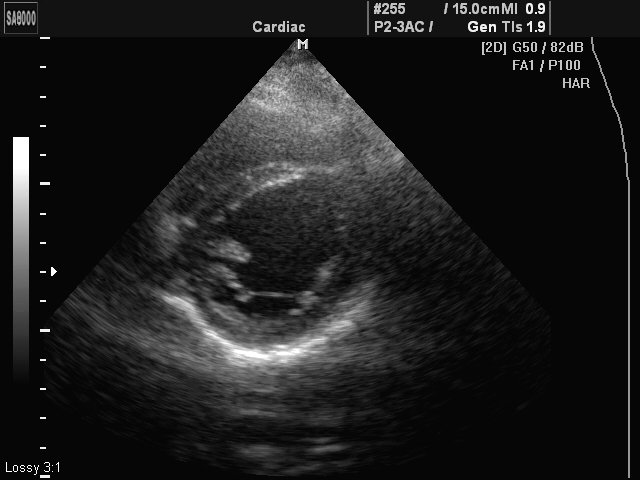

Additional hord of LV, B-mode (echogramm №426)

[RU] Ultrasound image №426: Heart (additional hord of left ventricle) in B-mode.

Echogramm was received by ultrasound scanner SonoAce-8000 (out of production).